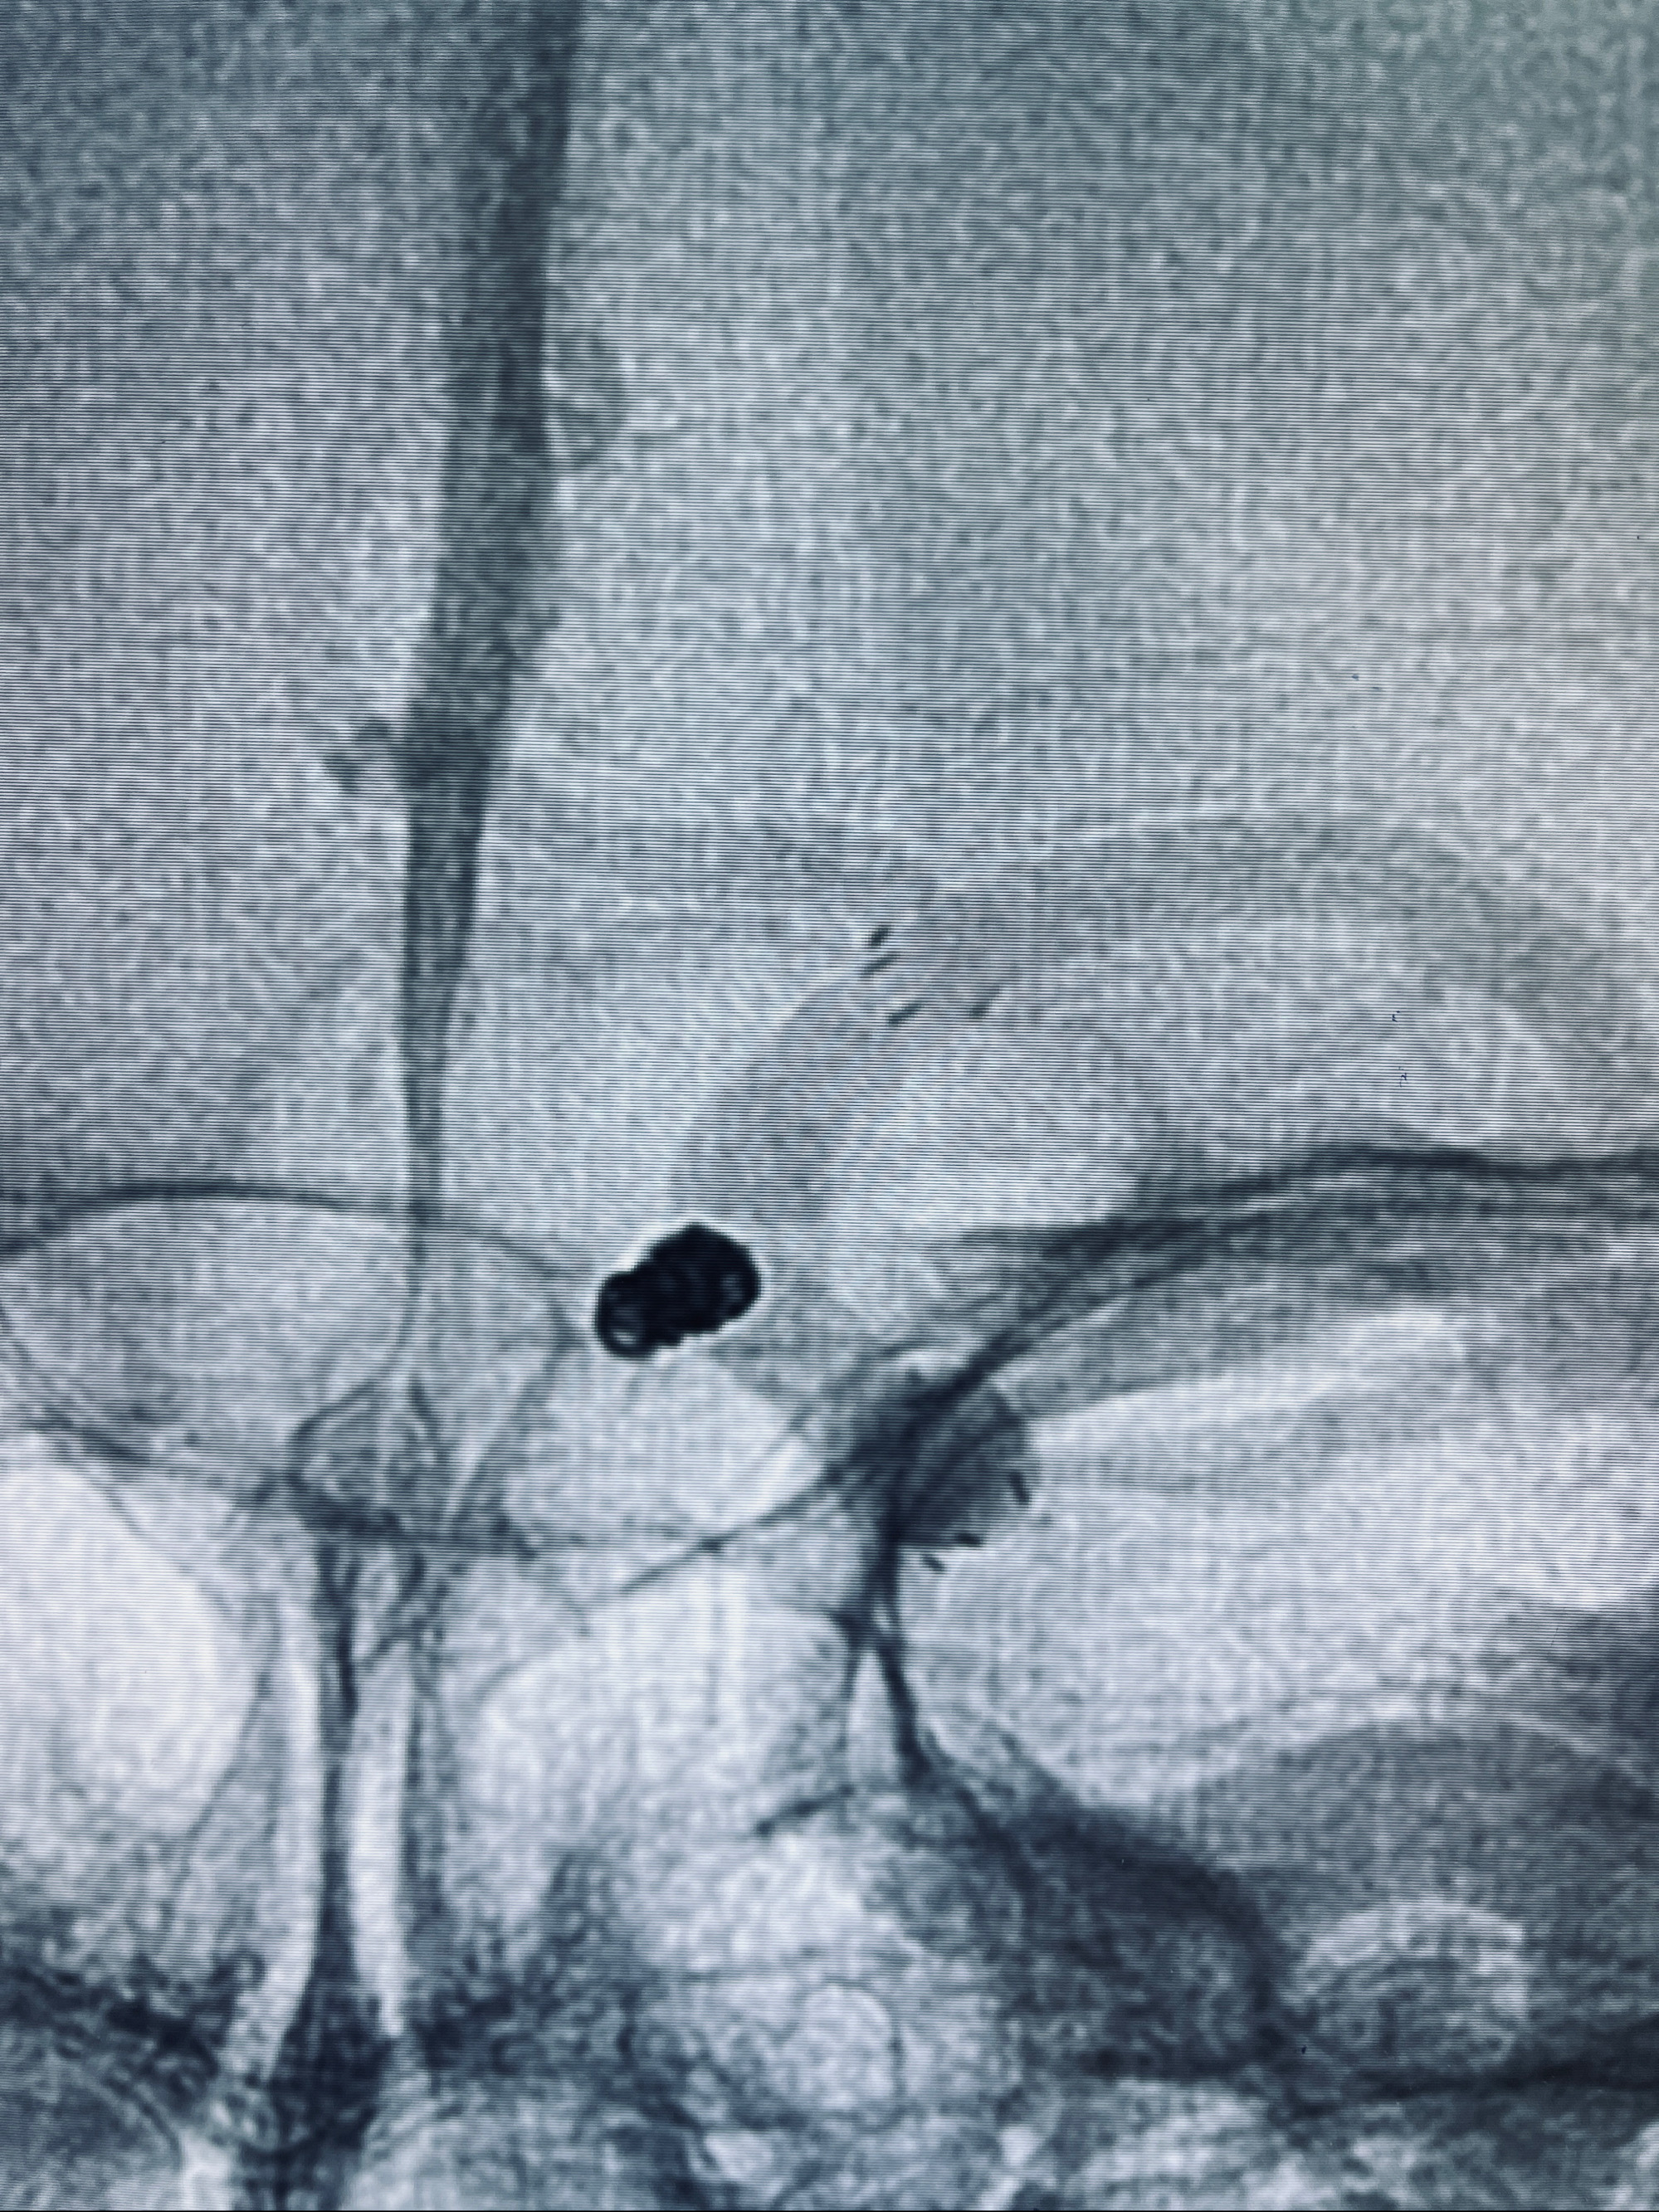

现病史:患者,女,因“左侧颈眼动脉瘤支架辅助栓塞术后1年余”入院。患者2021-5-24因“头晕”就诊于华山医院查头颅CTA、DSA诊断左侧颈眼动脉瘤,随后在全麻下行“左侧颈眼动脉瘤支架辅助栓塞术”,术顺,术后恢复可,予以阿司匹林、氯吡格雷抗血小板,阿托伐他汀钙片降脂稳定斑块。3月后华山医院复查脑血管造影动脉瘤未见明显复发或残留,停用降脂药物。目前患者无明显不适主诉,口服阿司匹林抗血小板治疗,为行脑血管造影收入我科。

1.左侧颈内动脉眼动脉段动脉瘤(支架辅助栓塞术后)

2022-09-29复查DSA

患者支架内血栓,给予阿司匹林+立普妥+依折麦布强化降脂干预